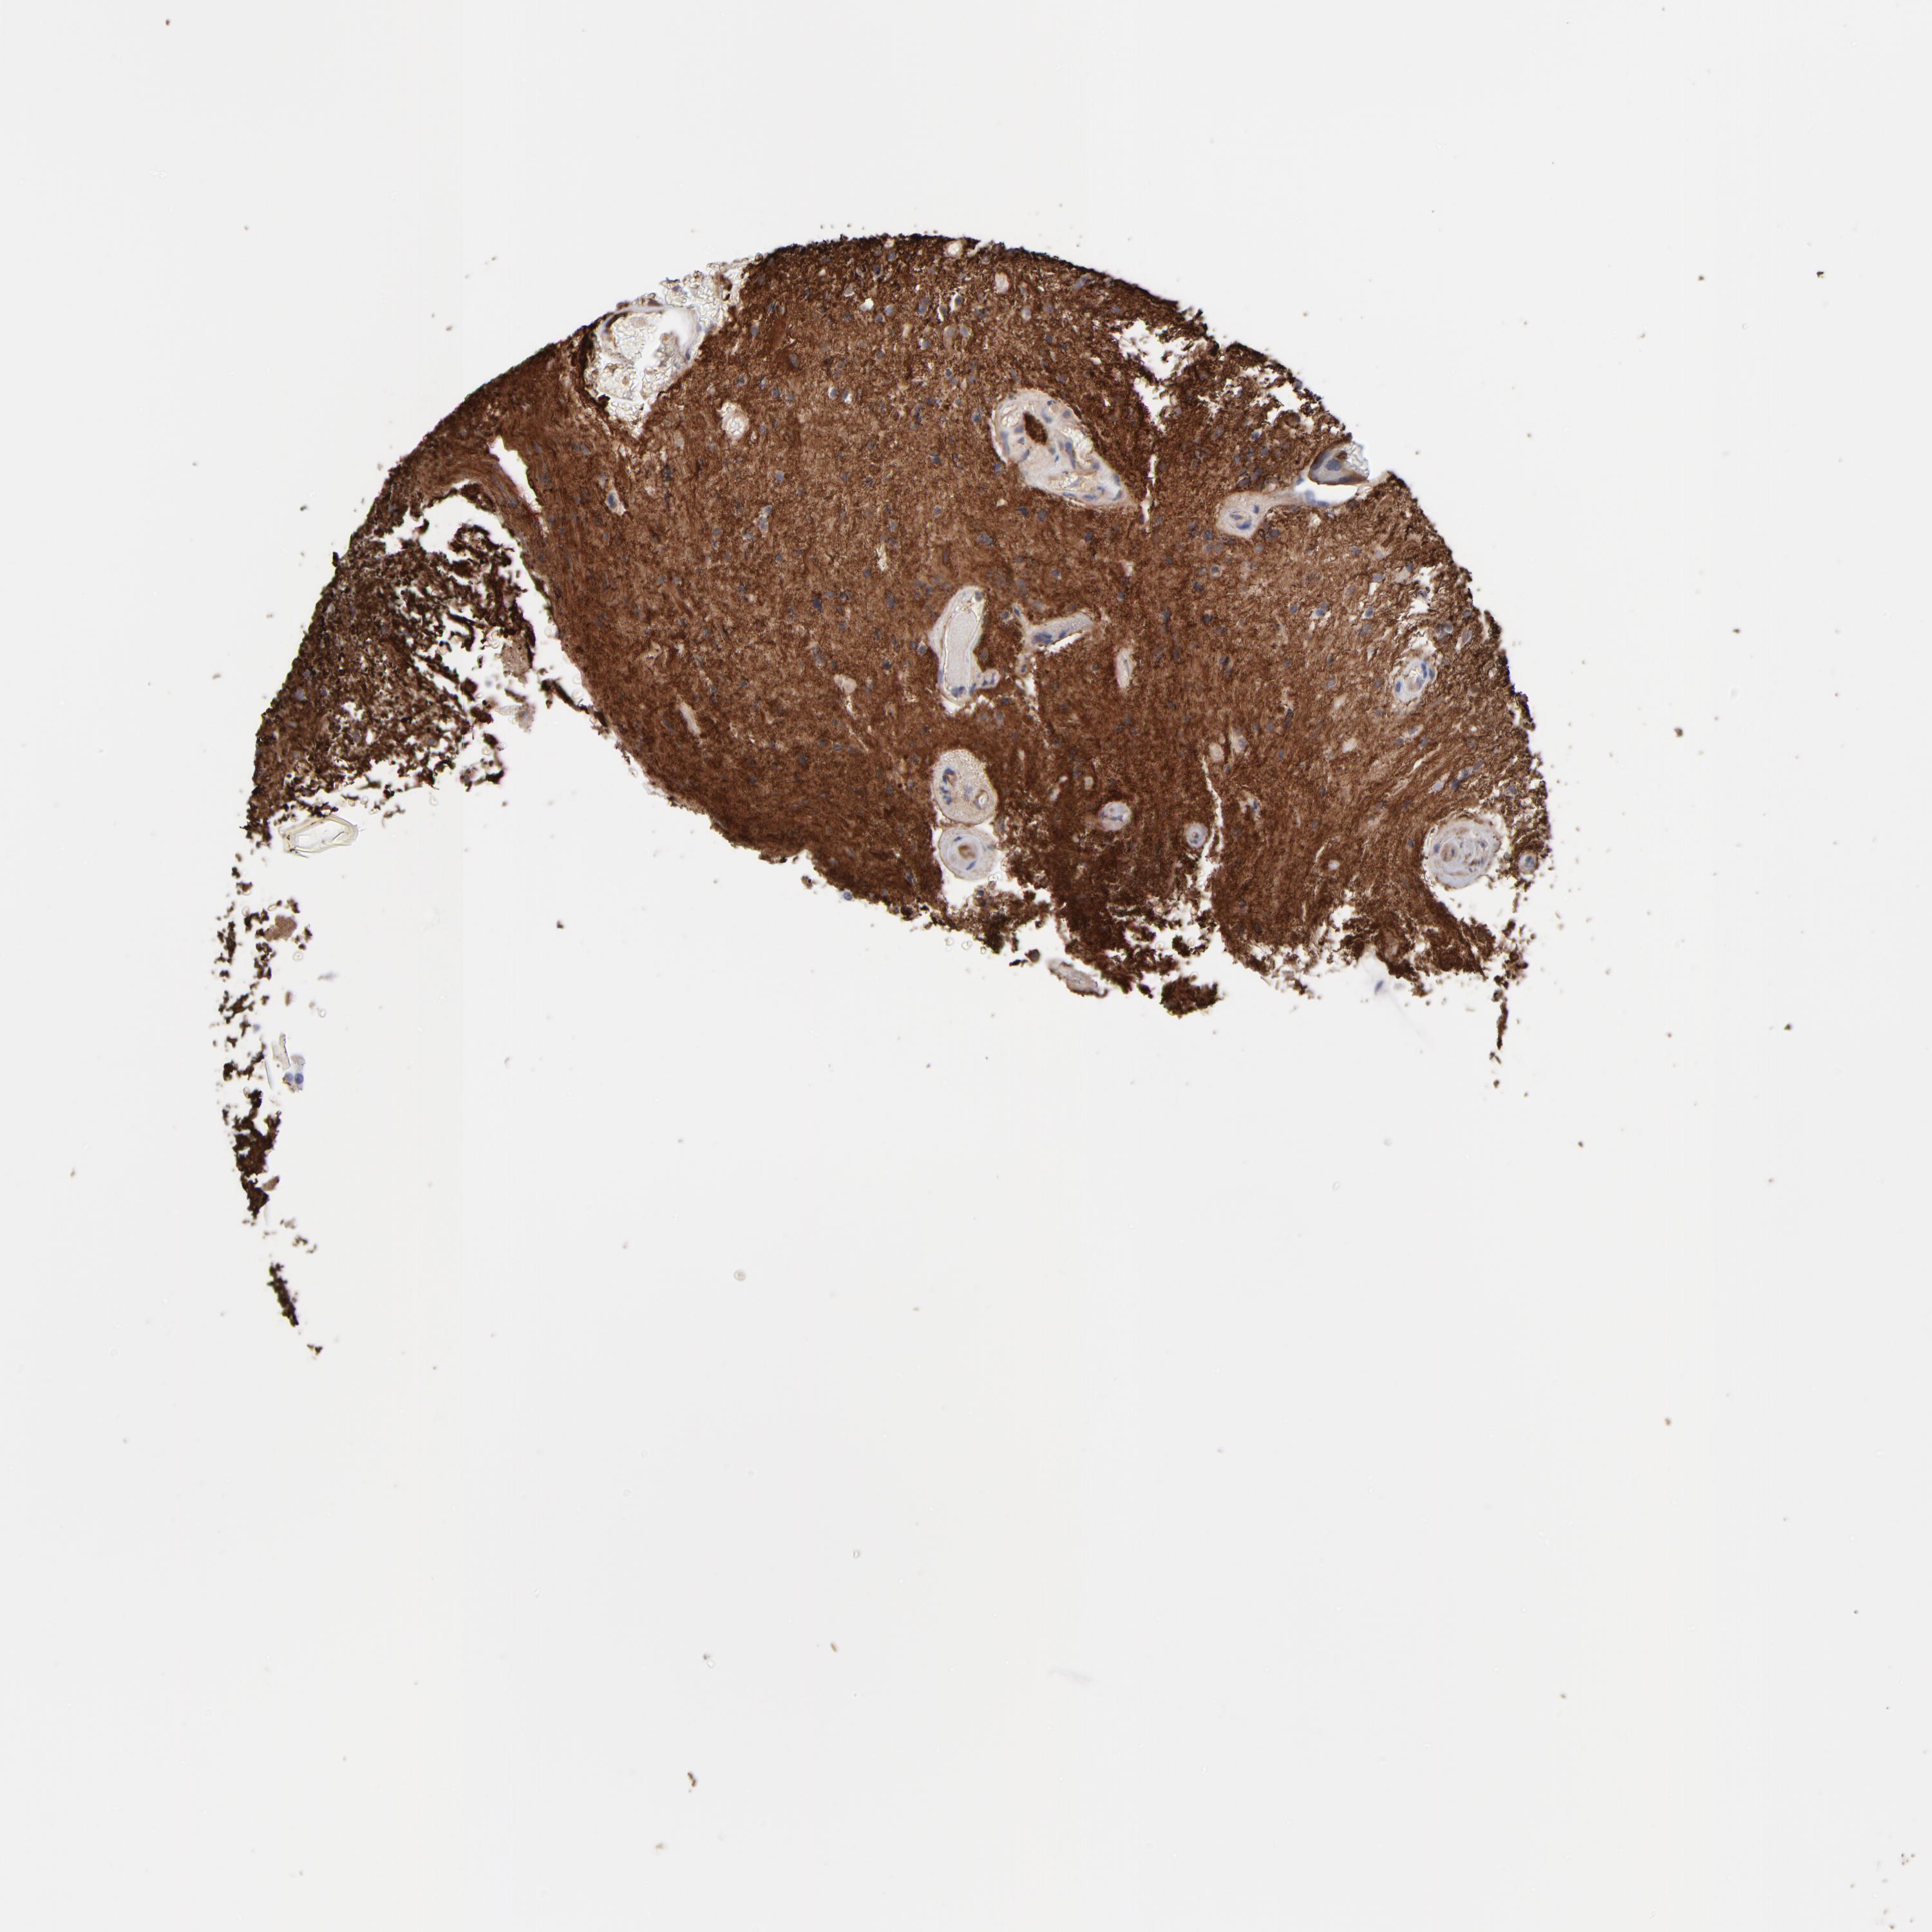

GLIOMA - Protein expressioni

A mouse-over function shows sample information and annotation data. Click on an image to view it in a full screen mode. Samples can be filtered based on level of antibody staining by selecting one or several of the following categories: high, medium, low and not detected. The assay and annotation is described here.

Note that samples used for immunohistochemistry by the Human Protein Atlas do not correspond to samples in the TCGA dataset.

Antibody stainingi

Antibody staining in the annotated cell types in the current human tissue is reported as not detected, low, medium, or high, based on conventional immunohistochemistry profiling in selected tissues. This score is based on the combination of the staining intensity and fraction of stained cells.

Each image is clickable and will lead to virtual microscopy that enables deeper exploration of all samples and also displays staining intensity scores, fraction scores and subcellular localization as well as patient and tissue information for each sample.

Antibody CAB003841

Staining

High

Medium

Low

Not detected

Intensity

Strong

Moderate

Weak

Negative

Quantity

>75%

75%-25%

<25%

None

Location

Nuclear

Cytoplasmic/membranous

Cytoplasmic/membranous,nuclear

Glioma, malignant, High grade

Glioma, malignant, NOS

Glioma, malignant, Low grade